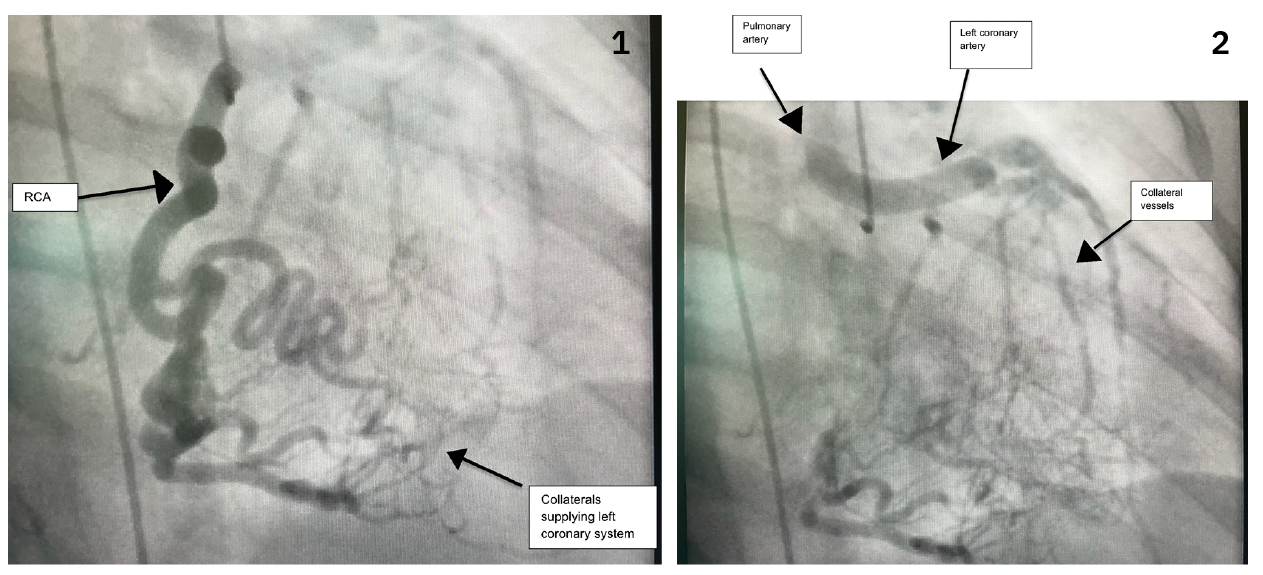

She underwent coronary angiography to assess for cardiac ischemia. Coronary angiography showed an anomalous left main coronary artery originating from the pulmonary artery, and supplying the left circumflex artery and left anterior descending artery. Angiography also demonstrated a very dilated right coronary artery supplying collaterals to the entire left coronary system and showing the left coronary artery emptying into the pulmonary artery (Figures 1-2, Video).

Video (below). Cine showing the right coronary artery with right-left collaterals filling the left coronary artery and pulmonary artery.